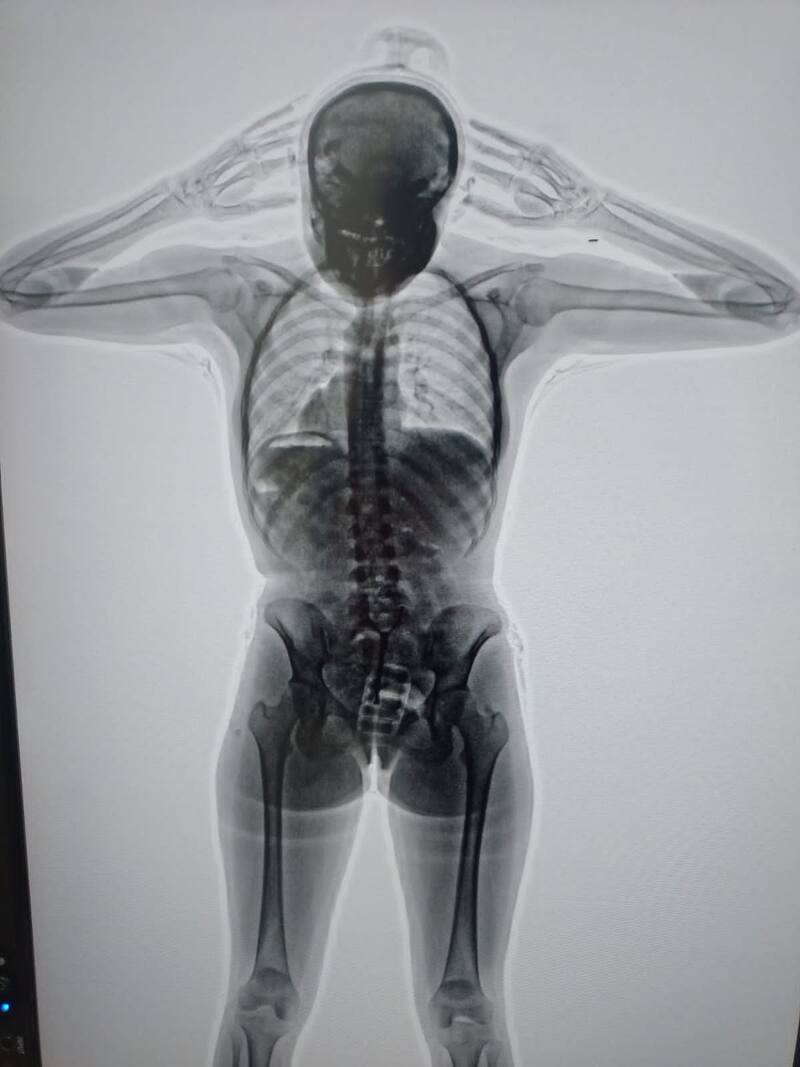

Cuando inspeccionaron las pertenencias no encontraron nada sospechoso, pero cuando la Policía de Seguridad Aeroportuaria (PSA) realizó un body scan se reveló qué ocultaba la pasajera.

Las imágenes mostraron la presencia de cuerpos extraños en su organismo. En concreto, había introducido en su vagina un profiláctico con 11 cápsulas de cocaína, de aproximadamente 10 gramos cada una.

En ese momento, la PSA y la Aduana dieron aviso a la Justicia y fue así que intervino el Juzgado Nacional en lo Penal Económico número 6, a cargo de Marcelo Aguinsky, que ordenó el traslado de la mujer al Hospital Eurnekian, en Ezeiza. Allí, bajo custodia de la PSA, estuvo incomunicada mientras evacuaba los cuerpos extraños advertidos en las imágenes del escáner. Estos resultaron ser 67 cápsulas más, dando un total de 78, con 742 gramos de cocaína.